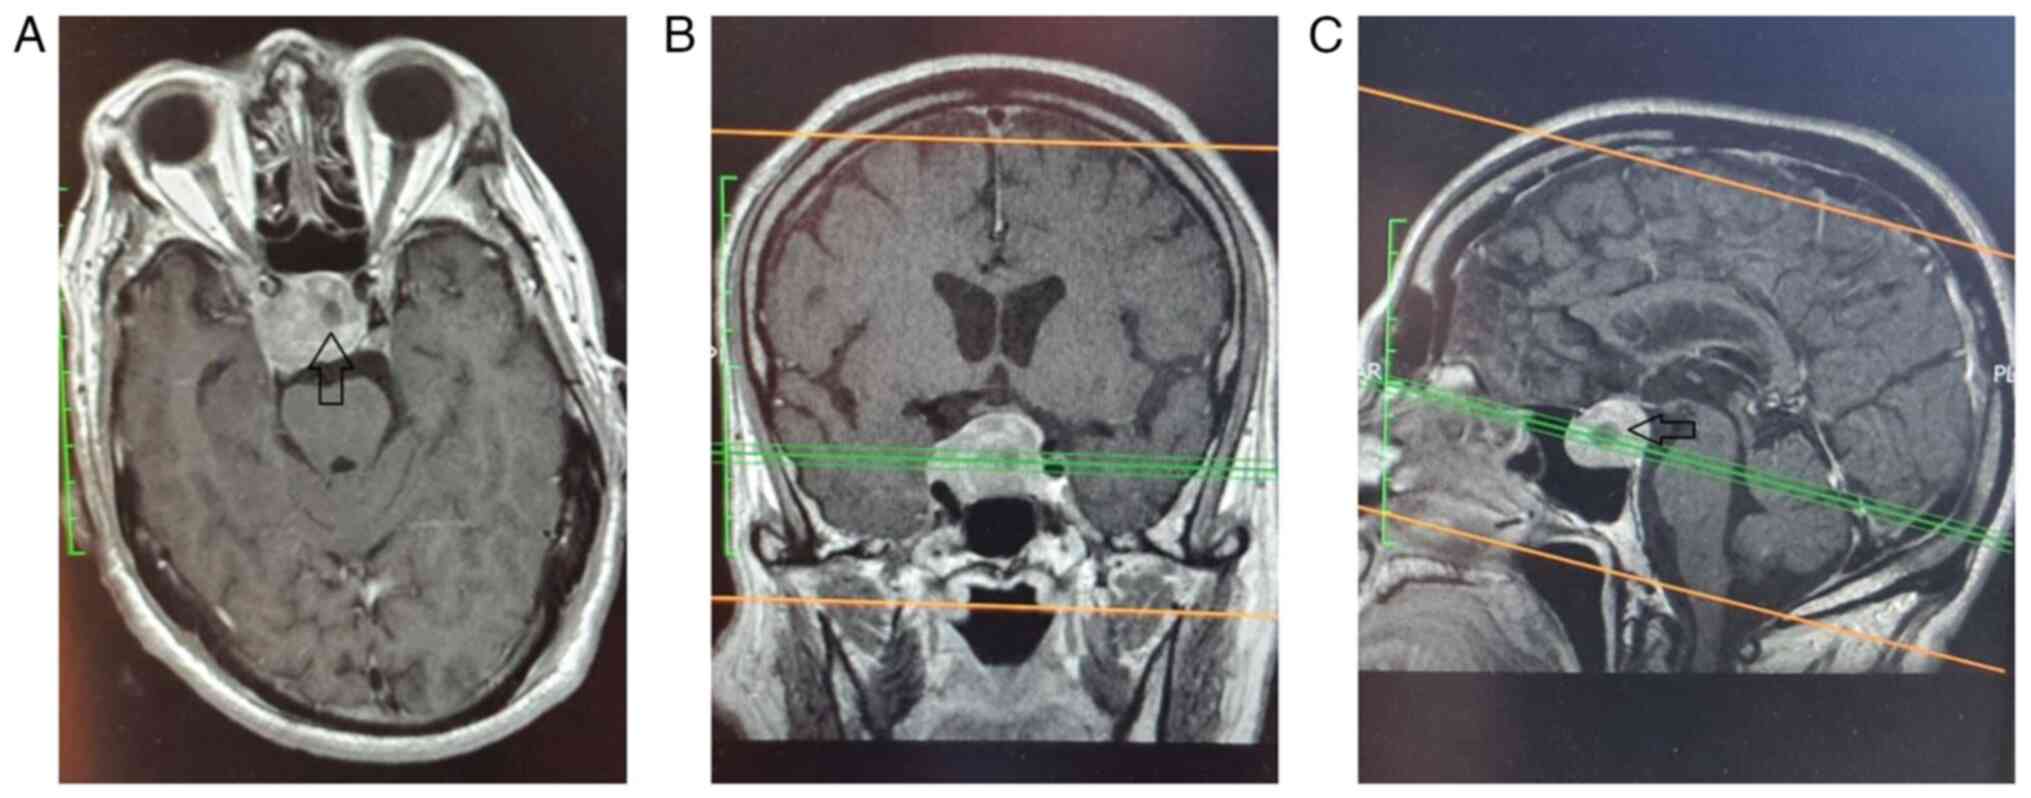

Figure 3

(A-C) Pre-operative contrast enhanced T1 MRI scan of patient 2, depicting a large pituitary macroadenoma that compress the optic chiasma (arrow).